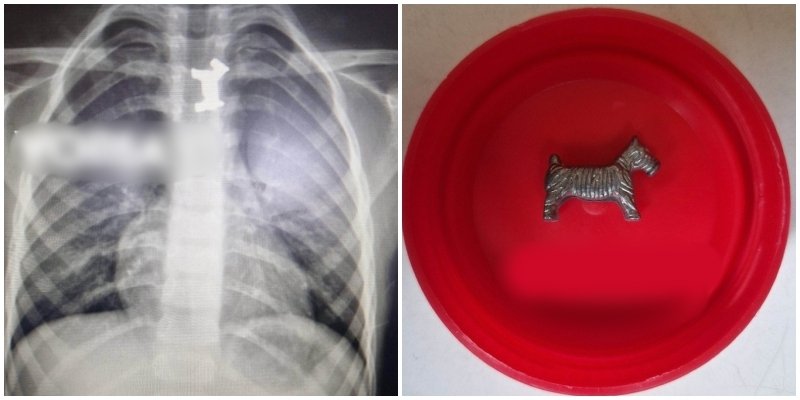

Siç raportojnë mediat greke, pas rrezatimeve dhe analizave imazherike, u konstatua se fëmija kishte gëlltitur një qen metalik gjatë një loje. Mjekët iu thanë prindërve se lodra duhej hequr menjëherë, pasi ndodhej në një vend mjaft të vështirë.

Pasi u bënë të gjitha analizat e nevojshme për lokalizimin e saktë të objektit, por edhe pas një vlerësimi pediatrik, fëmija iu nënshtrua një ezofagoskopie mëngjesin e sotëm kjo është një metodë për trajtimin e obstruksioneve akute të traktit të sipërm tretës tek fëmijët nën anestezi të përgjithshme për ta hequr lodrën nga ezofagu.

Mjekët hoqën me sukses lodrën metalike dhe fëmija është në gjendje të mirë shëndetësore dhe po trajtohet në Klinikën e Pediatrisë.